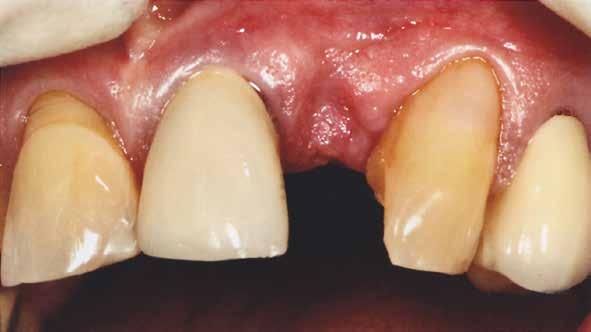

A 80 éves páciens 22-es fogának hiányát szerette volna megoldatni a rendelőben. Az implantációt költségessége miatt nem tudta vállalni. A 21-es fog már koronával volt ellátva, és kategórikusan elutasította ennek lengőtagos híddal való lecserélését, így egyértelmű volt a 23-as fogon való rögzítés szükségessége.

Az egyszárnyú ragasztott híd mellett döntöttünk (1. a kép)

Mivel a szemfogak általában nagyon közel vannak az antagonistához, kettes pótlására a szárnyat inkább a nagymetszőre szoktuk tervezni. Ehhez persze invazív preparációra van szükség – érintetlen fogak esetén ez lehetőleg kerülendő.

A bemutatott esetben azonban könnyen döntöttünk, mivel a szemfog disztális részén nagy tömés volt. A defektust bevontuk az eset megoldásába.

A cikkben egy fiatal nő kezelésének interdiszciplináris megközelítését foglaltuk össze, aki fogászati állapota miatt hoszszú ideje szenvedett fizikálisan és pszichésen is (1. ábra)

Amikor a 25 éves Andrea először konzultált a rendelővel, már több éve küszködött súlyos panaszokkal. Állapota két különböző betegségnek köszönhető, melyek egyrészt önmagukban, másrészt egymással kölcsönhatásban is súlyos következményekkel jártak. A fiatal nő veleszületett genetikai elváltozásban szenved, melynek tünete többek között a gyenge zománcfejlődés. Továbbá a beteget fibromyalgiával is diagnosztizálták, mely krónikus fájdalom rendellenesség, ami komoly tünetegyüttessel járó pszichés szorongás. A betegség egyik következménye az volt, hogy a páciens az elmúlt években átlagosan napi három-négyszer hányt. Az ebből fakadó savas erózió a már amúgy is veszélyben lévő fogazatot tovább roncsolta (2. ábra)